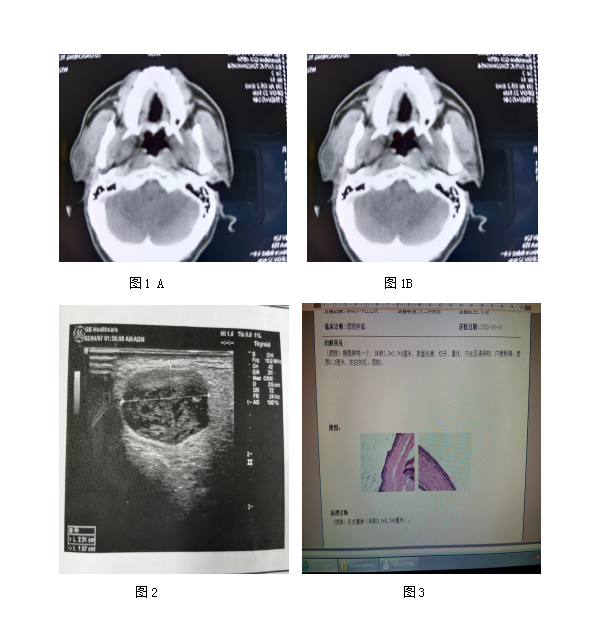

男性患者,52岁,左腮腺区肿胀1月余,既往体健。查体发现:左侧耳后区局限性稍隆起,无压痛,实验室检查未见明显异常。CT检查:左侧腮腺区偏后极部3.5mm*2.5mm*2.0mm不规则低密度影(图1A),CT值约26HU,与腮腺分界清,报告提示考虑腮腺囊肿可能。CT增强检查后发现实性部分呈明显不均匀强(图1B),囊性部分后缘强化,颈部未见肿大淋巴结,考虑腮腺囊肿,不排除外鳃裂囊肿。B超检查显示,左侧腮腺内低密度回声,考虑腮腺内囊肿(图2)。行全麻下腮腺肿物切除术+面神经解剖术,术中左侧腮腺区白色肿物,最大径约30mm,质软,与面神经分界不清。病理检查:光镜下见肿物内含部分“豆渣样”物,其内见大量镜影细胞灶,局部伴钙化,周围上皮细胞围绕,上皮细胞似呈星网状层分化,周边呈栅栏状排列 (图 3),病理诊断显示为皮样囊肿(左侧腮腺区异位)。

皮样囊肿属先天性疾患,是一种错构瘤,常位于皮下,偶见于黏膜下或体内器官。皮损组织病理显示囊肿为单房,囊壁较厚,类似完整或不甚完整的皮肤结构。最内层为角质层,其余各层为颗粒层、棘细胞层和基底层及真皮层。真皮组织可见有毛囊、皮脂腺、小汗腺和顶泌汗腺等组织。囊腔内可见皮脂、上皮碎屑、毛发和较黏稠液体。囊壁包含皮肤附属器结构如毛囊、小汗腺、大汗腺,偶尔可包含牙齿或神经。本例皮样囊肿发生于左侧腮腺区,影像学表现符合囊肿特征,具有高度诊断价值。皮样囊肿的鉴别诊断:①鳃裂囊肿,多为单囊性,信号均匀,少见钙化;②多形性腺瘤,多见于中年患者,肿瘤内部可见钙化。另联合进行CT及MRI检查对诊断皮样囊肿具有重要意义。